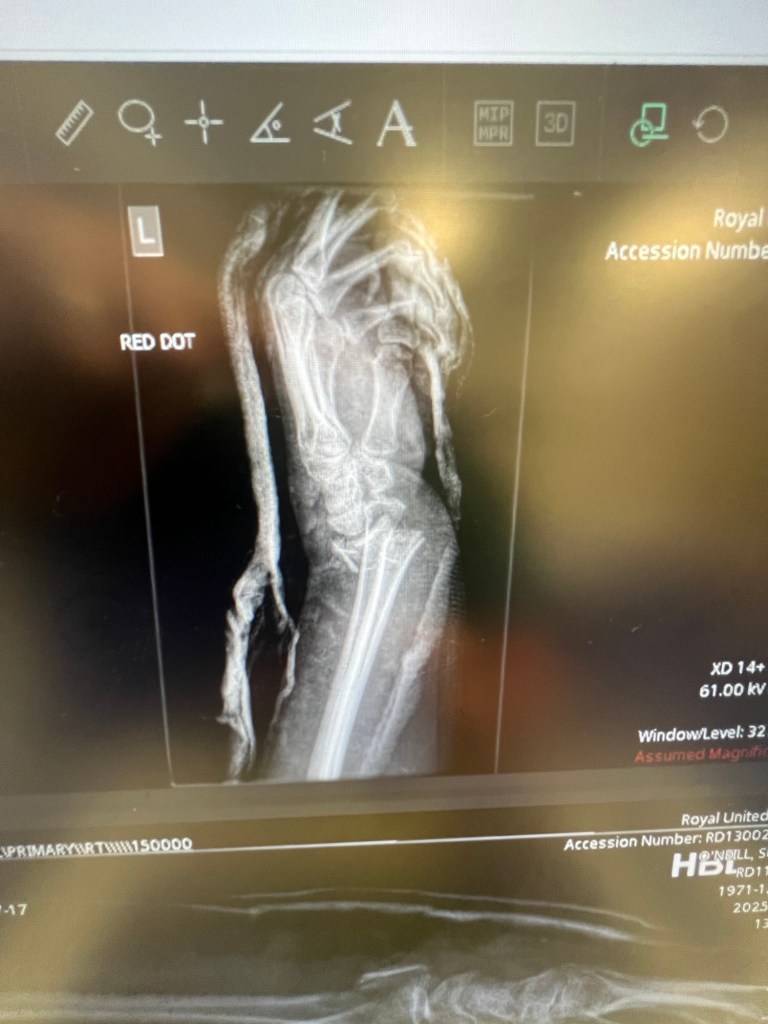

Honestly, giving birth will reign supreme as the most painful thing I have ever experienced, but breaking my wrist? That was hands down (hands down, heh-heh) a very close second. I remember I screamed. And kept on screaming. I forced myself to have a glance at my injured arm and I was nearly sick; yep, a classic ‘dinner fork’ Colles fracture (dinner fork in that my arm, bent as it was, resembled the shape of a dinner fork. Nice). No ifs nor buts, that bad boy was broken. Another chap came by on his commute to work and hesitantly offered to help – hoping no doubt that I’d say no – and luckily for him, I did. Still sobbing, I haphazardly dragged my phone from my bag and rang my boss. Like I say, she was only a few metres away and is a nurse – so I thought that was my best bet. We’ll call her Jackie (because that’s her name), and she came running out with my other colleague, who we’ll call Kathryn (also her name), to find me in a groaning, snotty heap at the bottom of the steps. I don’t remember a great deal about this time, thankfully, but I know Kathryn ran off to fetch her car and kindly drove myself and Jackie to the nearest Minor Injuries Unit (MIU). I know – in between crying and swearing – I briefly went into shock in the front passenger seat of the car (poor Kathryn must have been beside herself). And I also know the normally short drive to the MIU in the next town took an absolute age due to another road accident – just my luck. I’ve no idea what happened to that particular casualty and I’m afraid I’m going to have to leave it to him or her to write their own blog about that. If they’re able.

On arrival at the MIU, the attending nurse was pretty upfront about what little they could offer me, but it was felt best I was wheeled in anyway, and they could ring me an ambulance from there – since the big District General Hospital was over 10 miles away and we were in the middle of morning rush hour. The nurse rapidly gave me gas and air (there was no other pain relief available than that) and felt for a pulse. There was no pulse. Wonderful. And off she went to phone for an ambulance – I could hear her saying, ‘threat to limb‘ which is never a pleasingly pleasant phrase to overhear about oneself. But in hindsight, I now see that as a good thing since the ‘threat the limb‘ thing meant the ambulance was there in minutes. Now, as good as gas and air is (I mean, it ain’t great – but it sends you into this kind of trance which is better than screaming in agony), it was only aboard the ambulance on my way to the general hospital that they really managed to get the pain under control. Morphine is what you really need – and I did. After a couple of unsuccessful attempts to get a cannula in (my usually big veins, which I pride myself on, had decided to bugger off due to the shock, I guess), the marvellous morphine could be given. Unfortunately, morphine makes me vom – but luckily I knew this – so they administered an antiemetic along with it (an anti-sickness drug). The pain was manageable after that – down from an excruciating 1000/10 to about 6/10. After another seemingly slow and miserable journey, we arrived at the general hospital where I wound up on a stretcher in a kind of holding corridor with other fairly serious casualties – my lovely boss and the lovely ambulance crew waiting with me. But luckily I wasn’t there terribly long at all before two equally lovely nurses took me into the emergency department proper to first have an X-ray (which showed the fracture that was not a surprise to anyone). I remember the male nurse said, ‘oh, you’ve realllllly broken that‘), then I was whisked off to have a manipulation.

Jackie assures me the nurses looked positively gleeful about doing this – it appears to be one of those procedures that A&E staff get excited about. Obviously, like you, I’ve seen this done on TV and I was extremely anxious it was going to be horrendous – fearing the relentless screaming may start again. But I was given another kind of inhaler a bit like gas and air but WAYYYY better, and the two nurses set about pulling my arm from both ends to straighten out the bone. I have to say, I did not find that painful at all. And it was after the manipulation that the pain really went away. So another x-ray ensued to ensure the manipulation was successful (it was), then I was hurried off to the plaster room to fix that sucker in place.